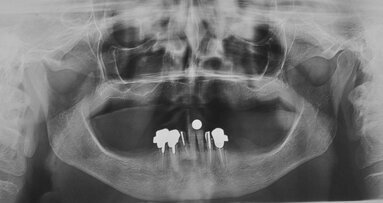

La paziente, B.G. di sesso femminile, di anni 71, è giunta alla nostra osservazione per la mobilità e lieve dolore a carico dell’elemento 2.2 (incisivo laterale superiore sinistro) (Fig. 1). All’esame ispettivo l’elemento presenta mobilità di grado 3. Al sondaggio parodontale presenta una tasca mesiale di 7 mm e di 3 mm lungo le altre superfici del dente. All’esame radiografico, eseguito con radiografia endorale periapicale, si osserva un’area di radiotrasparenza riconducibile a riassorbimento osseo soprattutto in sede mesiale (Fig. 2).

È stato inserito un impianto Straumann BLX 3.75 mm di diametro per 12 mm di lunghezza, con superficie SLActive seguendo l’asse protesico ideale (Figg. 4, 5). Avendo conseguito una stabilità primaria eccedente i 35 N/cm è stato realizzato un restauro provvisorio avvitato in composito su componente in Titanio da provvisori. Nonostante una sostanziale congruità della forma del provvisorio con la parte superficiale dell’alveolo, è stata utilizzata una matrice dermica suina (Botiss Mucoderm) allo scopo di sigillare il gap presente tra provvisorio e bordo mucoso dell’alveolo. Tale matrice, opportunamente sagomata e forata in modo da essere stabilizzata dal provvisorio stesso, è stata posizionata in modo da non rimanere esposta al cavo orale. Non sono state necessarie suture (Figg. 6-8).

A 7 giorni è stato eseguito un controllo per verificare lo stato dei tessuti gengivali e continuare a motivare la paziente riguardo all’esclusione dai carichi masticatori (Fig. 9). A 90 giorni è stato rimosso il provvisorio per procedere al restauro ceramico. Nonostante la superficie SLActive preveda un accorciamento dei tempi di integrazione, è stato deciso un tempo di attesa convenzionale per accertarsi della stabilità dei tessuti molli perimplantari (Figg. 10-12). È stato eseguito un workflow digitale a partire dall’impronta ottica, fino alla realizzazione di un restauro in Zirconia precolorata e stratificata vestibolare (Dental Direkt 1200 e Creation ZI-CT) su base titanio (Figg. 13, 14). Il restauro è stato consegnato mediante avvitamento a controllo di torque secondo le indicazioni della casa produttrice (Figg. 15, 16).

Fig. 5_Rx periapicale post-impianto.

Fig. 16_Controllo Rx post-consegna.